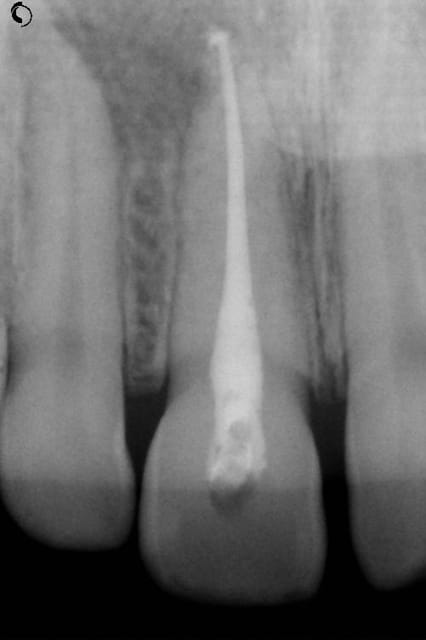

NB: ne pas chipoter svp sur l'appellation "kyste"

Kyste1 xpgssa - Eugenol

Kyste2 sef5wb - Eugenol

Repriseinit tk8kzi - Eugenol

Reprise4cx uandde - Eugenol